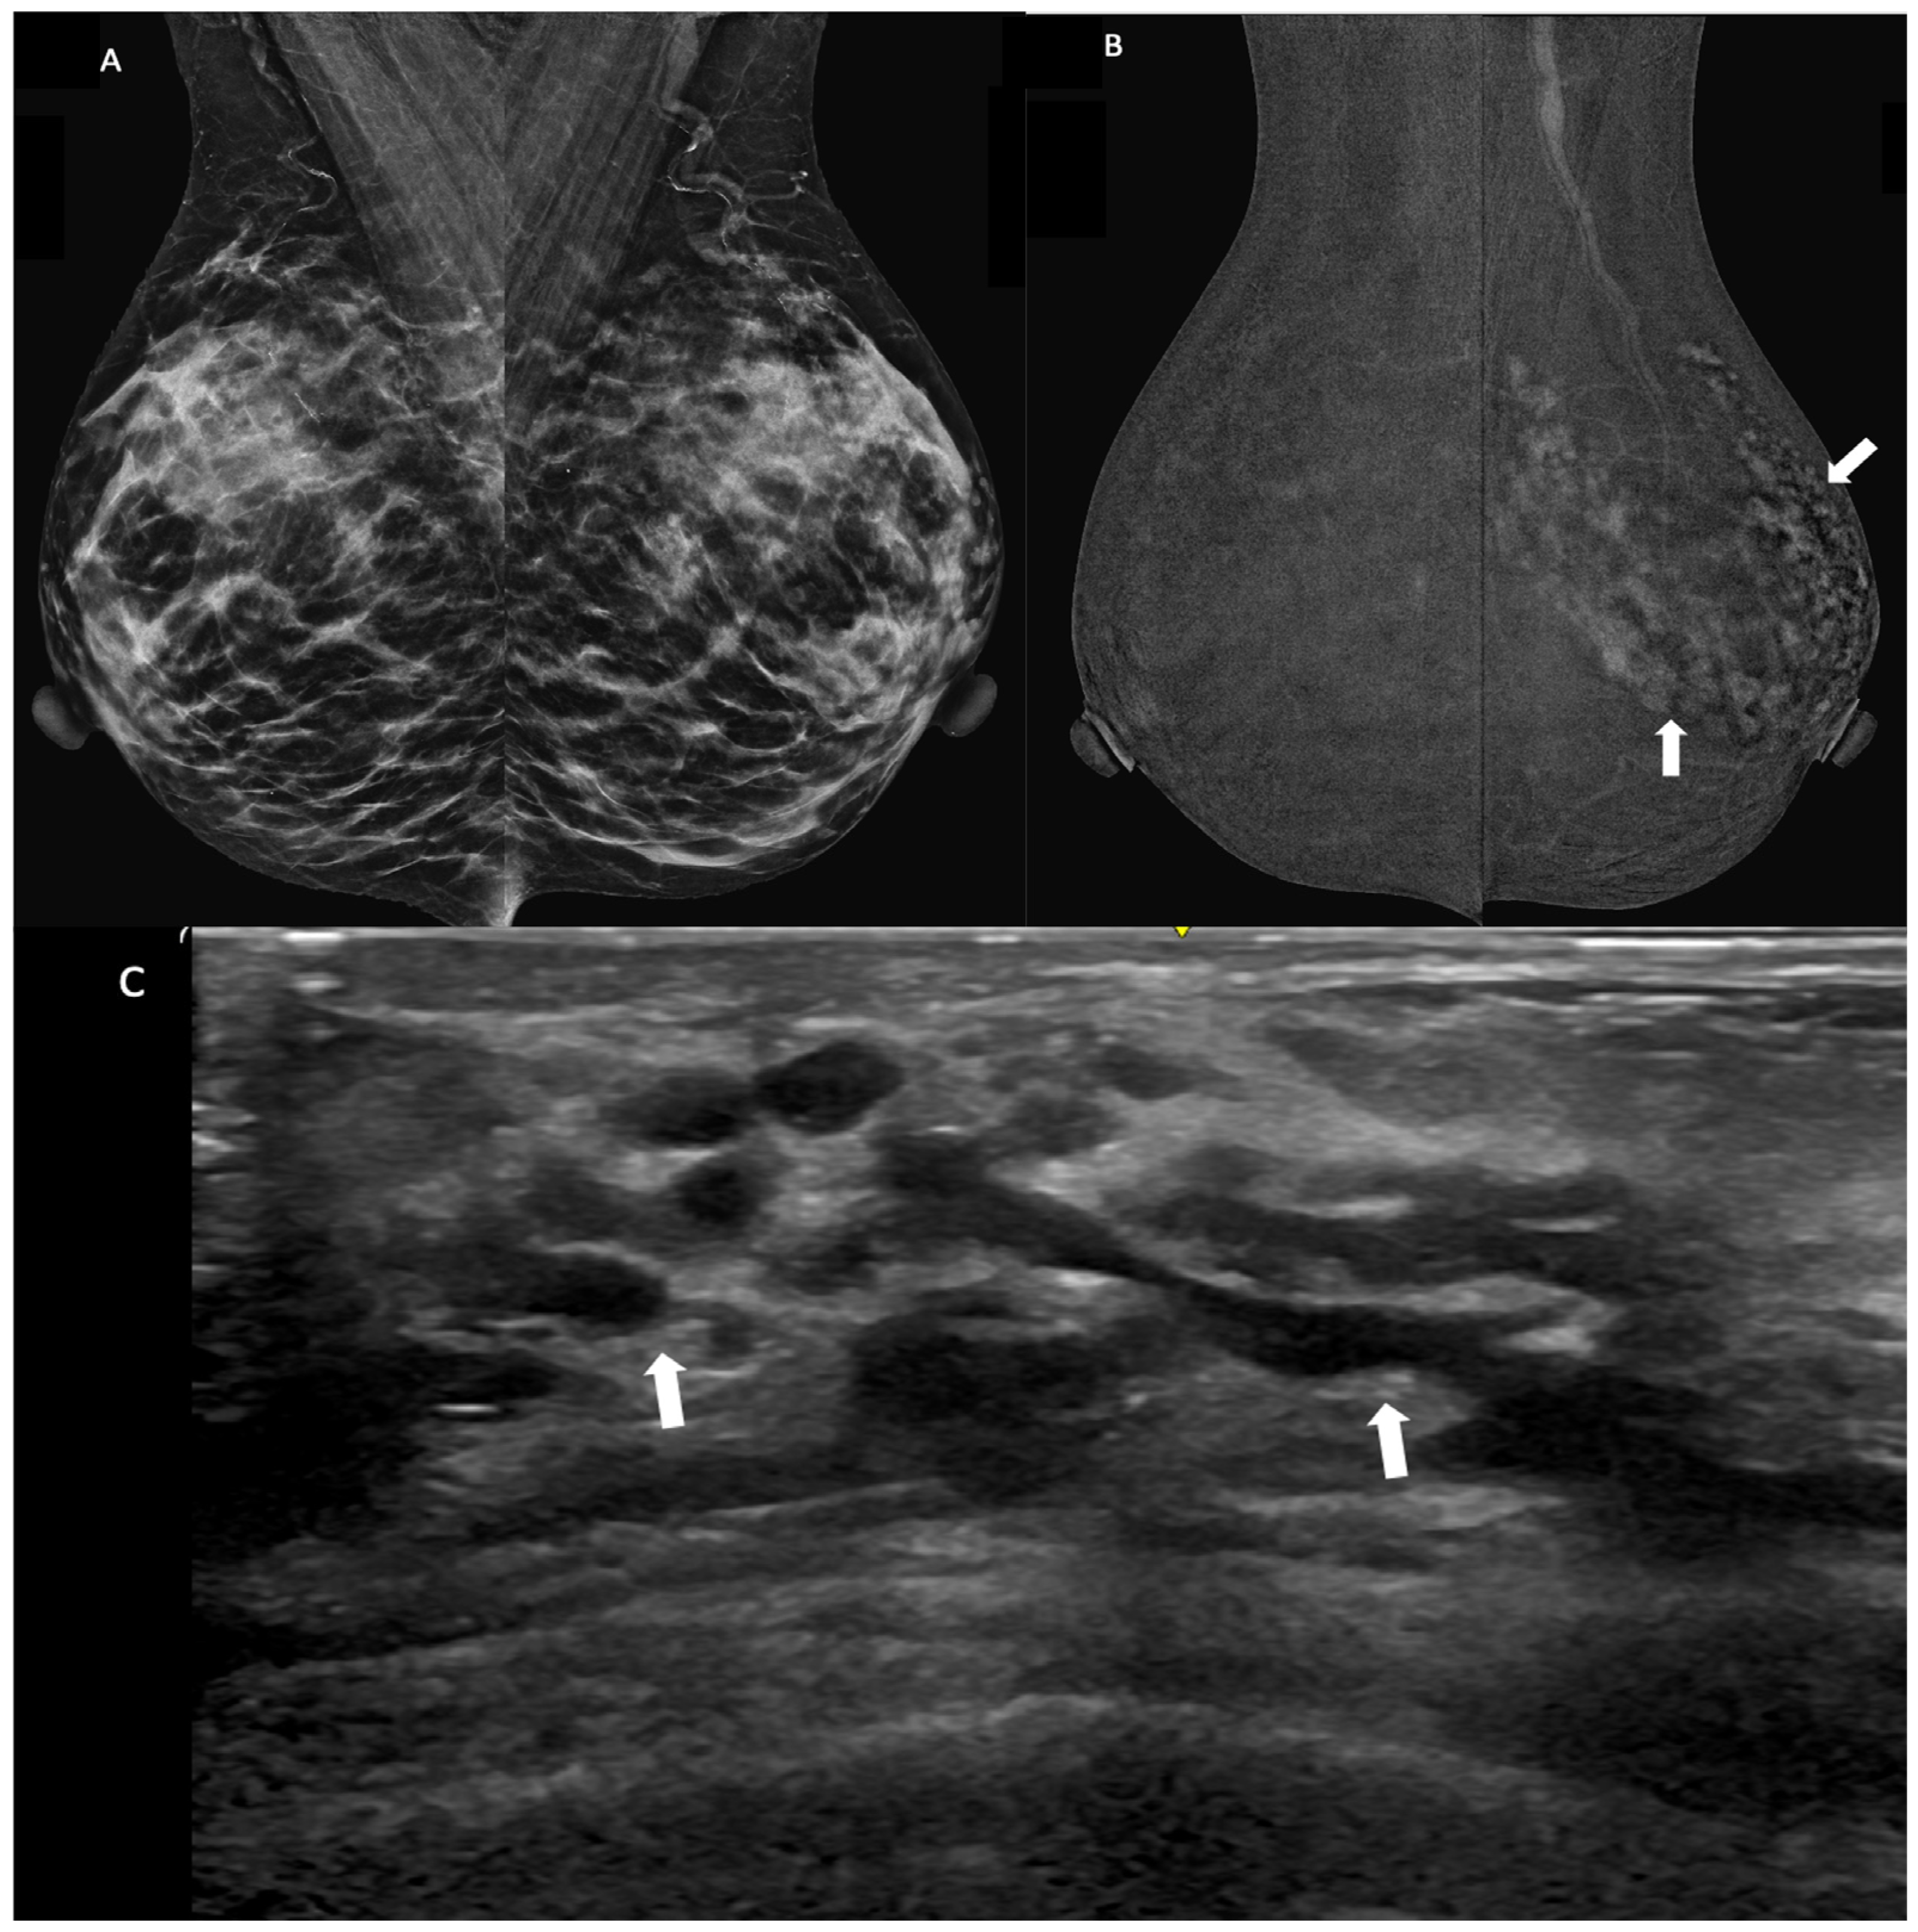

4.2. Benefits of CEM and Clinical Applications

4.3. Lesion Conspicuity

4.4. Morphpological Characteristics